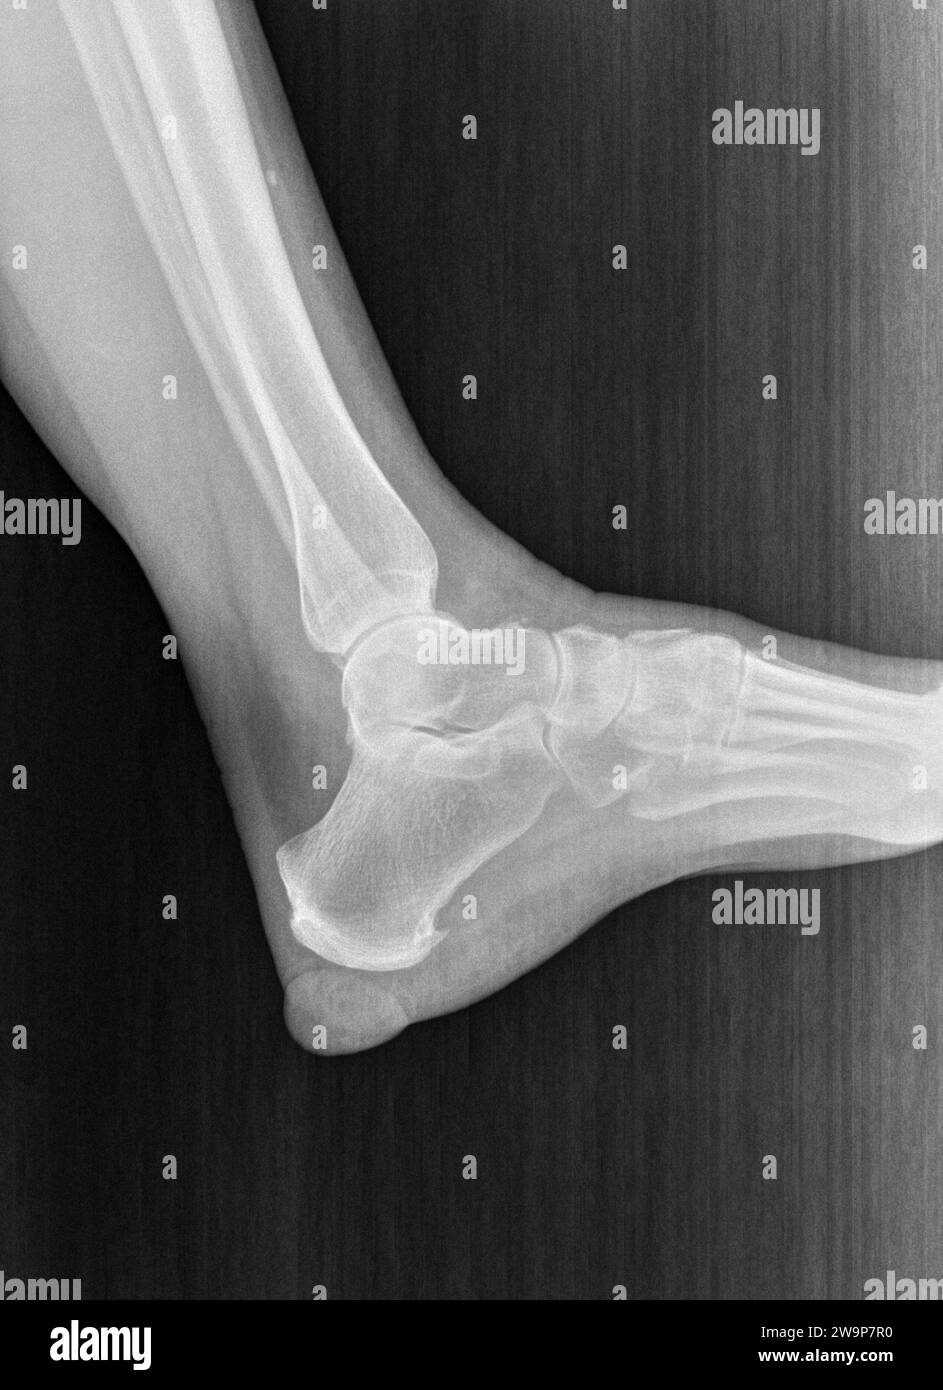

Film Xray or Radiograph of a Normal Foot, Ankle and Leg. Lateral View Normal Radiograph Of Foot normal right foot radiographs in a young adult female for reference. 17 public playlists include this case. 1 article features images from this case. this view demonstrates the location and extent of fractures in the foot, joint space abnormalities, soft tissue. The image displays the soft tissues and bones of your. diographs are essential for successful foot. Normal Radiograph Of Foot.